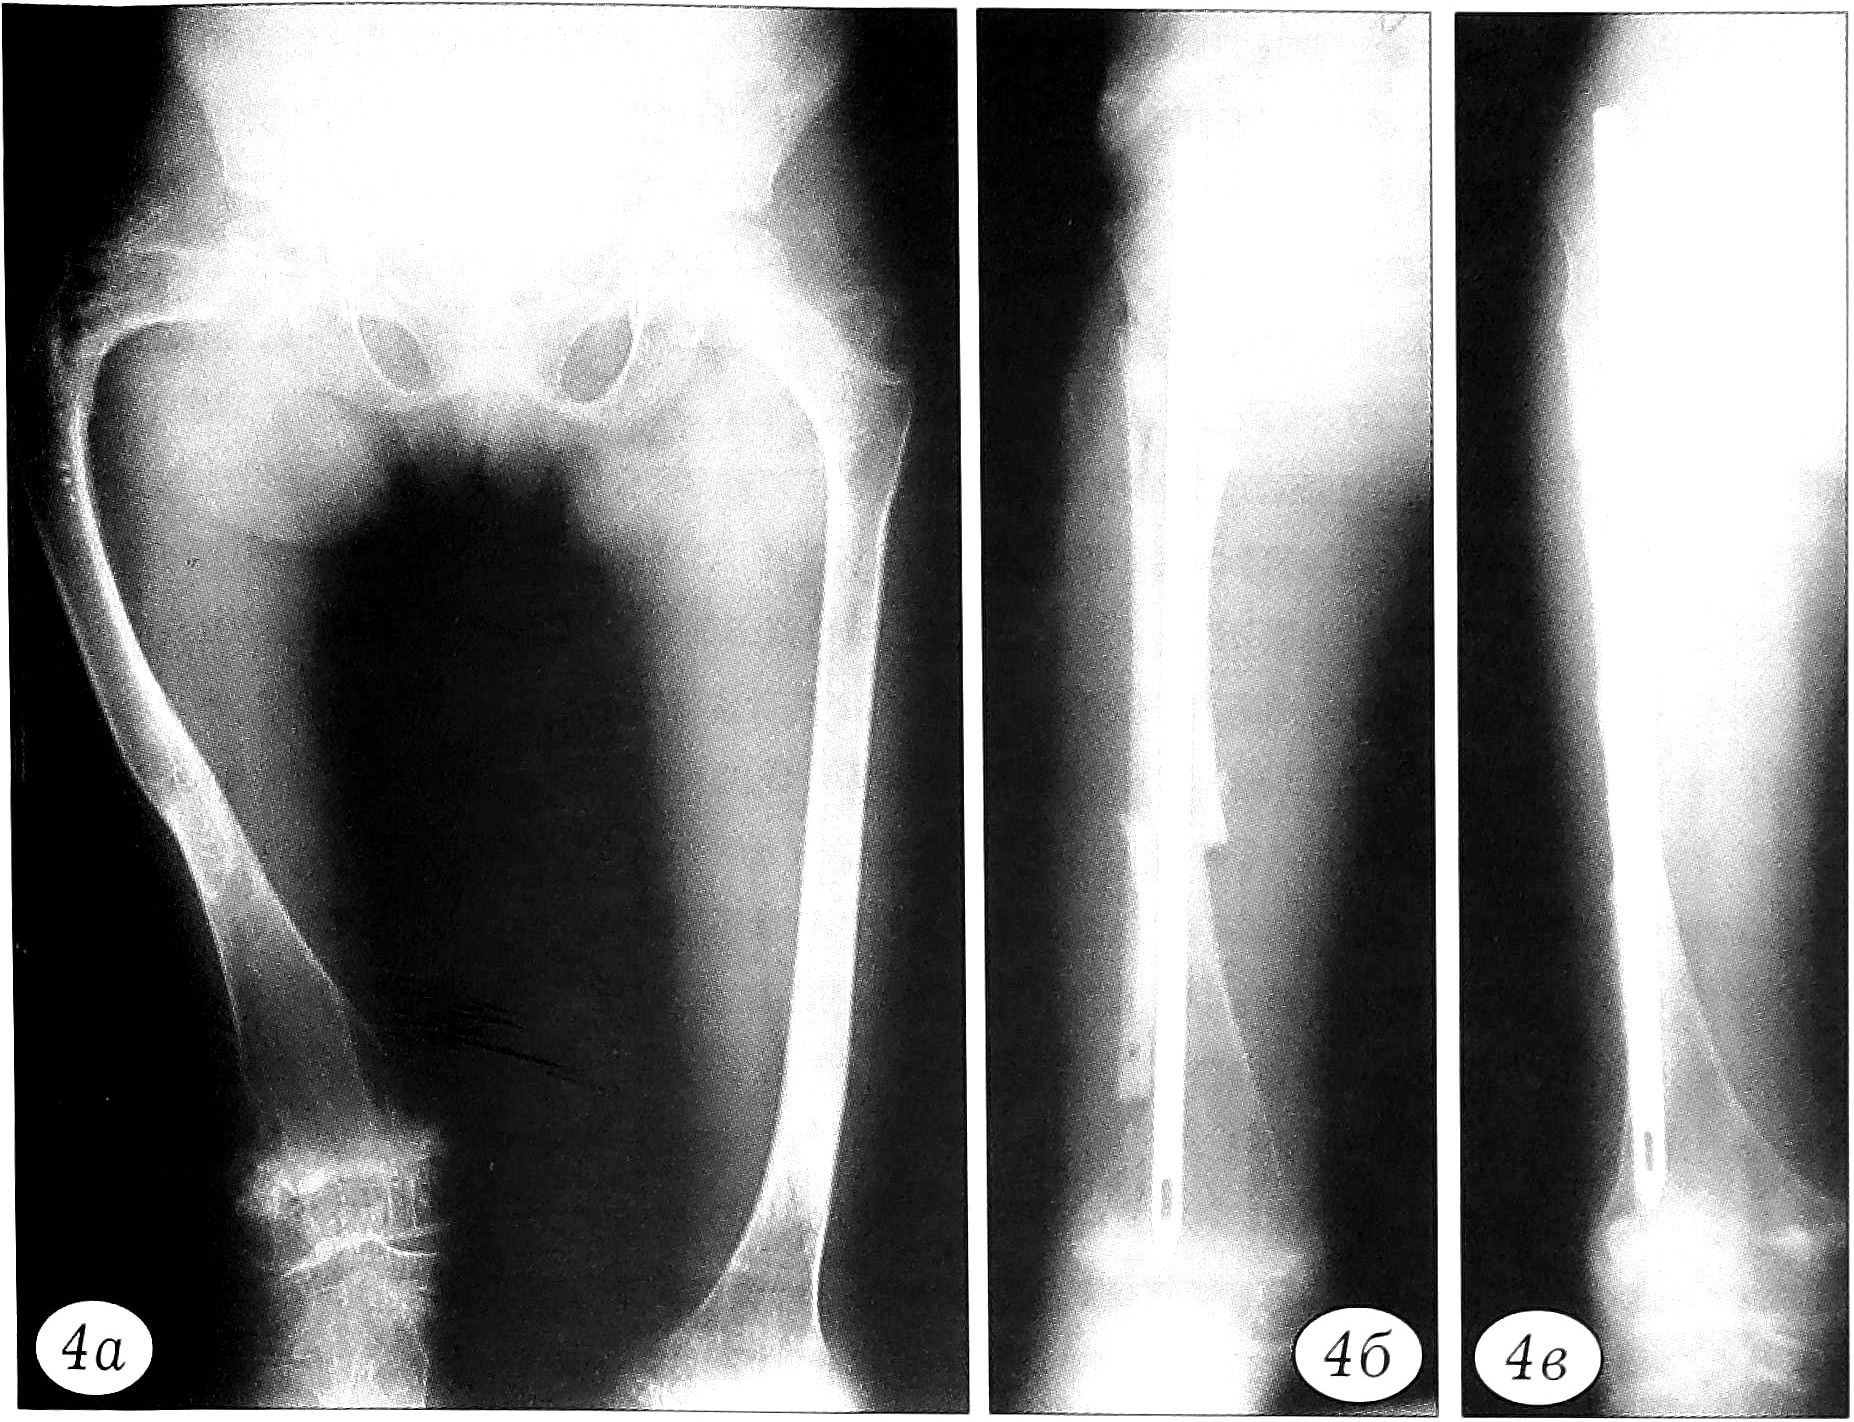

В случаях, когда требовалось не только заместить пострезекционный дефект, но и компенсировать укорочение пораженной конечности (2 пациента с болезнью Олье и 1 больной с кистой кости), использовали методику одномоментной костной пластики и удлинения сегмента на аллоимплантате в аппарате внешней фиксации (рис. 5). Показанием к компрессионно-дистракционному остеосинтезу являлись укорочение сегмента конечности более чем на 3-4 см и наличие патологического очага. При этом одна из задач аллопластики заключалась в предотвращении прорезывания спиц аппарата. Спицы проводили через пластины «Перфооста», которые одновременно служили фиксатором и материалом, замещающим дефект.

Рис. 5. Рентгенограммы больного Ф. 15 лет. Укорочение правой плечевой кости на почве солитарной кисты. а — до операции; б — после краевой резекции верхней трети плечевой кости, аллопластики «Перфоостом» и удлинения на имплантате в аппарате Илизарова в течение 14 дней.